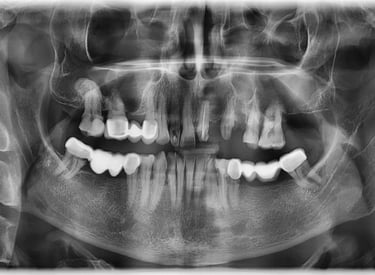

Reabilitare orala prin inserare a 3 implanturi dentare la nivelul cadranului II. In acelasi timp chirurgical s-a realizat aditie osoasa prin elevatia mucoasei sinusale in vederea asigurarii suportului osos necesar aplicarii implantului posterior.